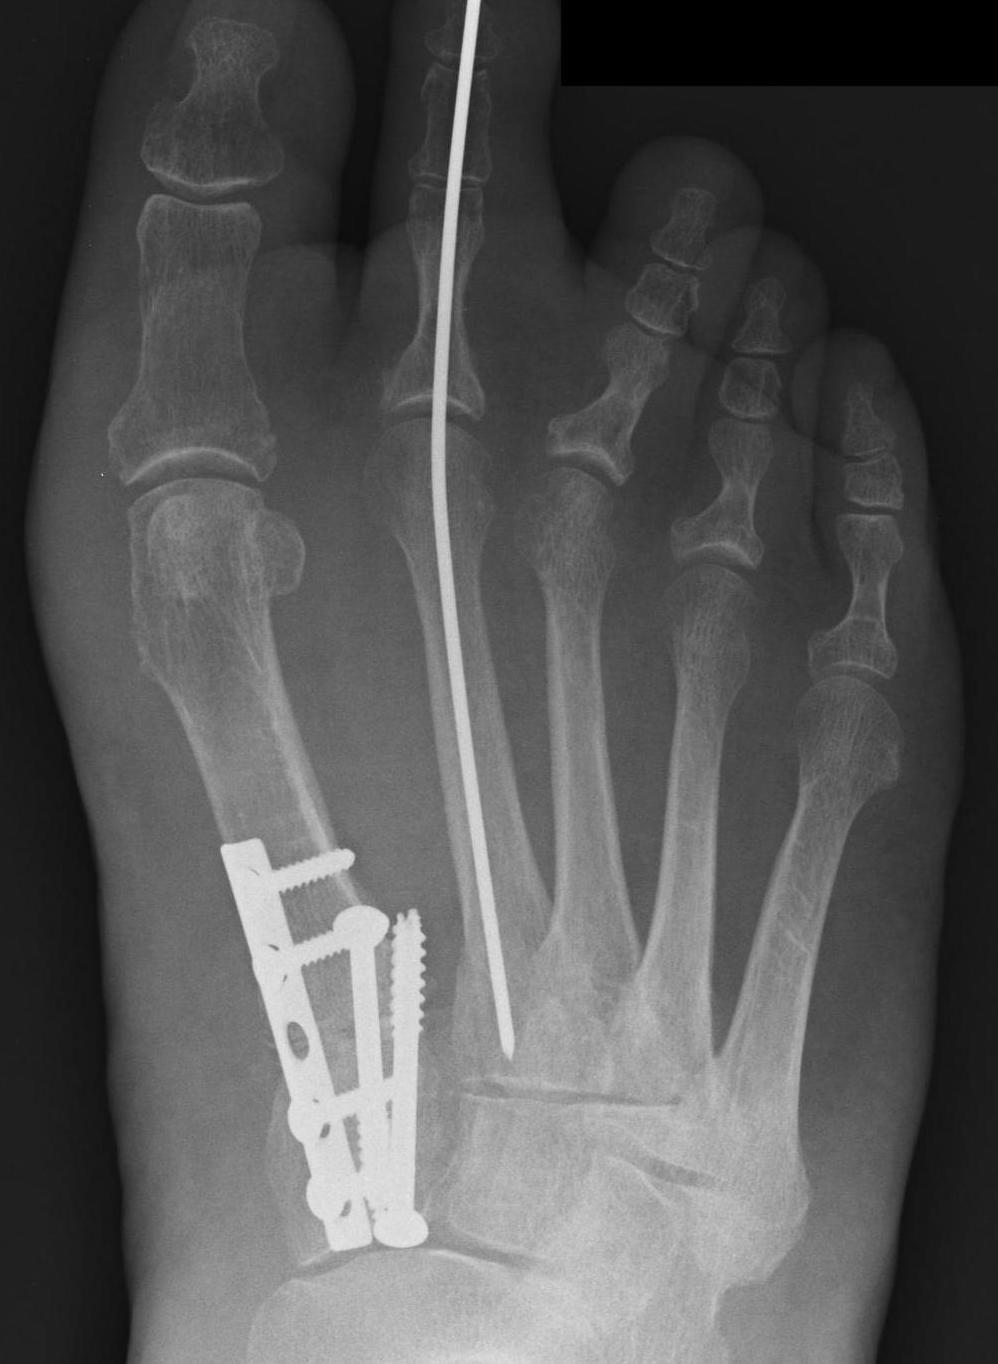

Lapidus Procedure / TMT arthrodesis + DTSP

Indications

- moderate to severe HV

- TMTJ hypermobility

- metatarsus primus varus

Technique

Triplanar correction - coronal / sagittal / rotational

Results

Do et al Orthop Clin North Am 2022

- systematic review of 1800 Lapidus

- complication rate 17%

- hardware pain 3%

- nonunion 3%

- delayed union 2%

- wound complication 1%